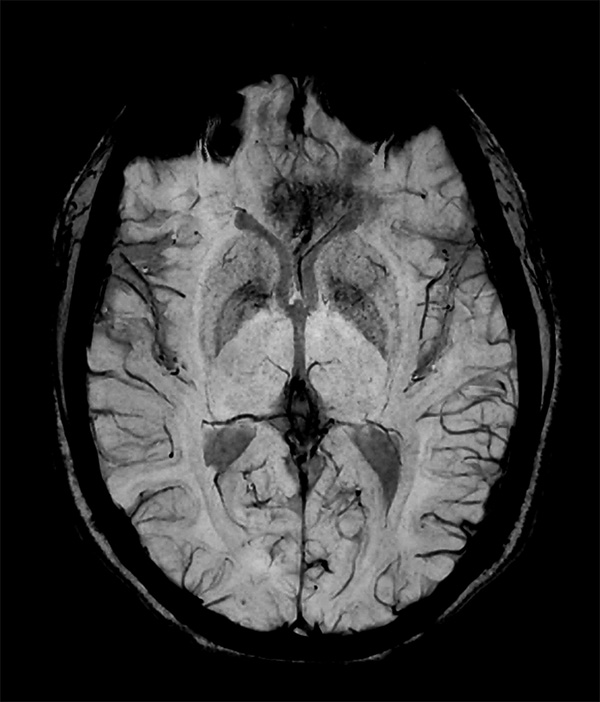

Comprehensive Brain imaging at 3.0T

• Clinical Application